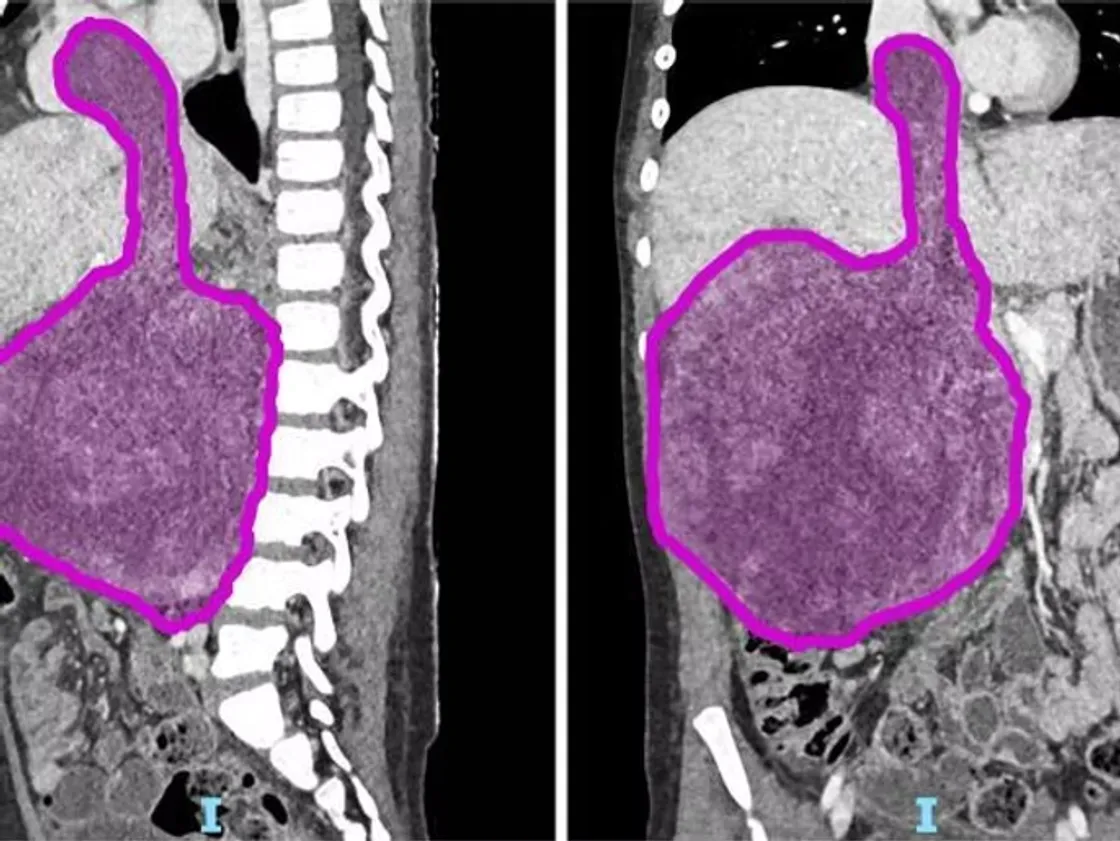

La bambina era affetta da un nefroblastoma, noto anche come tumore di Wilms, una forma rara di tumore renale pediatrico che colpisce prevalentemente i bambini tra 1 e 5 anni. Il tumore, del peso di 1,5 chilogrammi, aveva invaso il cuore, complicando ulteriormente la situazione clinica.

Per rimuovere completamente il tumore, l’équipe medica ha dovuto fermare temporaneamente il cuore della bambina, una procedura estrema ma necessaria per garantire la sicurezza durante l’asportazione del voluminoso nefroblastoma.